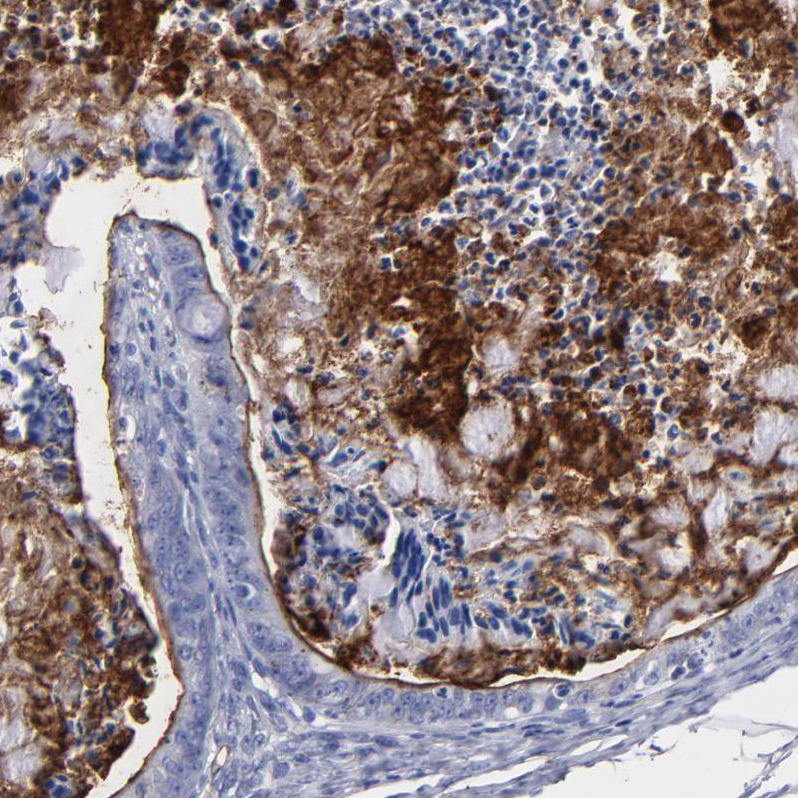

Immunohistochemical staining of human Ovarian cancer shows strong positivity in tumor cells.